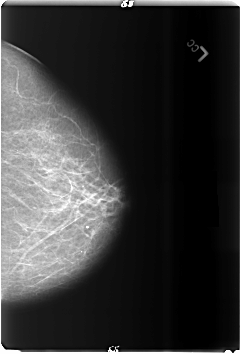

B_3489_1.LEFT_CC

LEFT_CC LINES 6008 PIXELS_PER_LINE 4080 BITS_PER_PIXEL 12 RESOLUTION 50 NON_OVERLAY